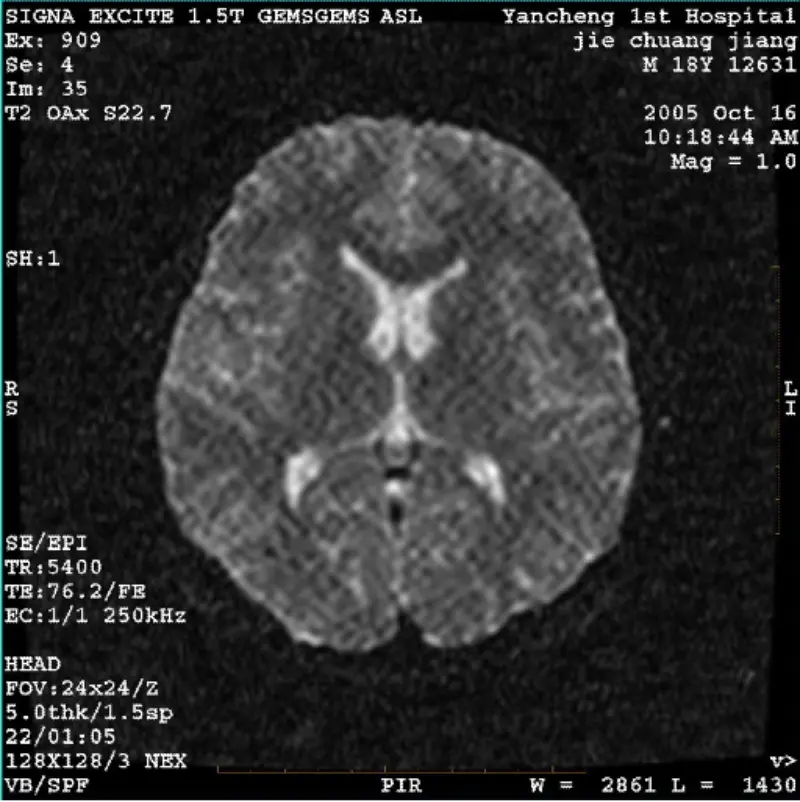

Đọc thêmHỆ THỐNG: 1.5T Signa Twin Excite II (Phiên bản phần mềm 11.0M4) VẤN ĐỀ/ TRIỆU CHỨNG Hình ảnh DWI (Chế độ thu phóng và toàn bộ chế độ) và fiesta (chế độ thu phóng và toàn bộ chế độ) có tạo tác dạng lưới hoặc vải nhung có thể nhìn thấy bất kể khi sử dụng cuộn dây trên thân hoặc đầu cuộn dây, hì......